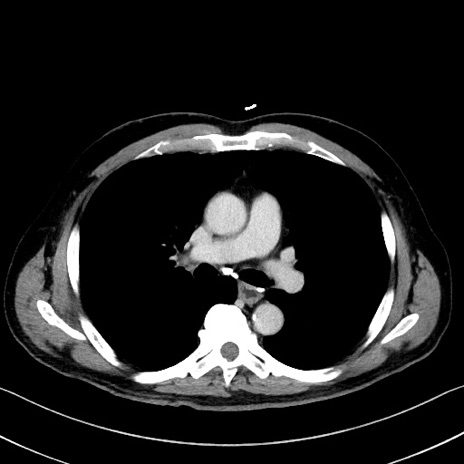

症例35(横断像)

【症例】70歳代 男性

【主訴】腹部膨満、嘔吐

【現病歴】昨日より腹部膨満感出現。本日増悪し、仙痛出現。嘔吐あり、受診。

【既往歴】糖尿病、胆摘後

【身体所見】BP 149/80mmHg、HR 74/min、BT 35.9℃、腹部:膨満、軟、圧痛なし。腸雑音減弱あり。上腹部正中切開瘢痕あり。

【データ】WBC 13500、CRP 1.72